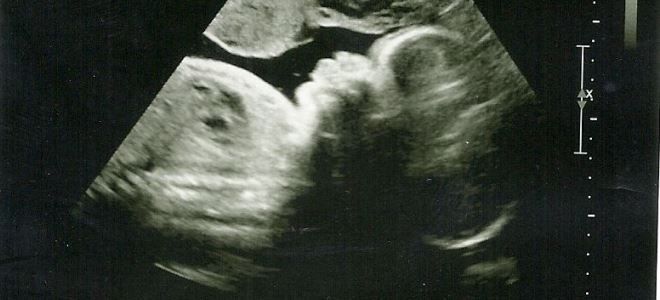

Как выглядит ребенок на 33 неделе беременности?

На 33-й неделе беременности плод внешне практически не отличается от новорожденного. Его тело покрыто значительным слоем первородной смазки, которая играет важную роль в облегчении процесса родов, позволяя ребенку безболезненно пройти через родовые пути. Пропорции тела становятся идеальными, а щечки малыша округляются. Кожа приобретает привычный оттенок: краснота и лануго (пух, который помогает поддерживать тепло) исчезают. Волосяной покров на голове становится более густым. Начинают проявляться характерные черты лица, что позволяет увидеть сходство малыша с мамой.

Положение плода на 33 неделе

На данном этапе беременности врачи часто назначают ультразвуковое исследование, чтобы выяснить, как расположен плод в матке. На 33-й неделе беременности переворот малыша уже невозможен, и специалисты могут точно определить тип предлежания. В зависимости от положения ребенка в утробе, медицинские работники разрабатывают стратегию для предстоящих родов.

УЗИ на 33-й неделе беременности выполняется исключительно по медицинским показаниям. В этот период назначается третий скрининг для женщин, у которых ранее были обнаружены отклонения в результатах обследований. Специалисты анализируют темпы роста плода, состояние его отдельных систем, а также положение плода в материнской утробе.